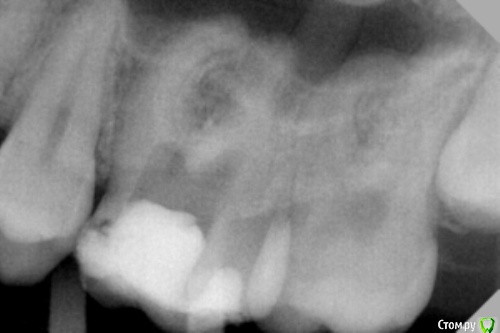

dr.Dre Опубликовано 16 апреля, 2016 Поделиться Опубликовано 16 апреля, 2016 Добрый день коллеги,пациентка 17 лет 26 зуб,с проходимых каналов только небный,жалобы на ноющую боль.Как поступить в данной ситуации? Ссылка на комментарий

Fred Опубликовано 25 апреля, 2016 Поделиться Опубликовано 25 апреля, 2016 Для начала оцените успешность того, что вам получилось сделать. Гляди боль и пройдет. Зуб уже неплохо разбит, дальнейший поиск не имея опыта в таком деле будет приговор зубу. Просто знайте, что не всегда возможно найти и пройти каналы не угробив при этом зуб. 1 Ссылка на комментарий

vse32 Опубликовано 19 мая, 2016 Поделиться Опубликовано 19 мая, 2016 Присоединюсь ко всем вышеперечисленным советам.Но попрошу всех, у кого бывают проблемы с поиском каналов, вспомнить одно золотое правило.В канал, зачастую, можно зайти только под вполне конкретным углом. Отклонение - неудача. Устье есть, инструмент не лезет. Играйтесь с направлением инструмента.На снимке зуб как раз достойный моих нравоучений. Ссылка на комментарий

vse32 Опубликовано 22 мая, 2016 Поделиться Опубликовано 22 мая, 2016 устья что то на rg не увидел, и в канал бы не попал, не видя куда. Вот только куда бурить дальше если он на уровне бифуркации , страшно рассверлить псевдо ход ,без увеличения , без визуального контроля ? Про ходы, на сколько градусов можно отклонение ? Можно по подробнее ? У меня возникает следующая проблемма: верхняя челюсть, моляры,поиск дистально-щечного , когда кудельцы провели пульпотомию закрыли сицем , и все кирдык , опускаюсь ниже коронковой части и где должно быть устье иже ход канала продолжается цемент, убить готов, ей Богу . Хотя если остановится, и до завтра, пациенты отмечают снижение боли, но не ее отсутствие. После пары загубленных зубов при такой картине вообще останавливаюсь и отправляю на микроскоп или искать более опытных. После таких провалов страшно вообще что либо переплачивать. А условия острая боль и отсутствие rg в отделении и такой сюрприз в зубе доводит до белого каления и без того разкочегаренное место. МБ обезболить и отсылать на rg? Гуру госок отзавись =)) http://www.edentworld.ru/u6.jpghttp://s020.radikal.ru/i709/1605/0e/d7c330b0ead6.jpghttp://s019.radikal.ru/i619/1605/86/2bd730811cd7.jpgЭто левый верхний первый моляр.Что-бы зайти в МД - инструмент вводим от середины - медиальной стенки или чуть более небно, острота угла вариабельна.А что-бы зайти в МБ1 - инструмент, фактически нужно положить из области дистального небного бугра, острота угла вариабельна.Я не претендую на звание гуру Госа, но 15 лет я там отбарабанила.1 год в интернатуре - без рентгена, без наставника, без приличных материалов и инстументов. Контингент - Ветераны труда со склерозированными каналами. После этого могла лечить периодонтиты "силой мысли", и выходить с голыми руками на медведя. )))Потом еще 14 лет в более благоустроенной поликлинике. Там, считай все супер было. Рентген был 4 часа в смену (смена 6 часов). Если, конечно рентгенолог не болел, не учился или в отпуске не был. А у них эти периоды часто и надолго. Только хождение пациента от меня до рентгенолога и обратно занимало от 10 до 50 минут. Диагностика периодонтита и контроль пломбировки еще туда-сюда, а вот сделать серию снимков во время ретрита - утопия. Тут то и развивается чутье в пятой точке. ))))Если что рядом была частная клиника, куда можно было в случае отсутствия снимков направить пациентов. Минус, снимки приходили на А4 на обычной бумаге.Материальное обеспечение вполне неплохое. Что не давали, докупали сами, так как начальство в то время лояльно относилось к подработкам врачей.Отсюда вопрос. Я вижу в профиле местоположение Сибирь. Я думаю в Сибири есть достаточно крупные города, а есть сильно помельче. В каком городе работаете Вы? В Москве, на данный момент, устроится в простенькую клинику, но с рентгеном и кальцием - не самая большая проблема. Зарплата, по любому, будет выше чем в сейчас в Госе.Второе, что Вас держит в таком убогом Госе? Возможность набить руку? - так Вы своих результатов не видите. Возможность подработать - тогда покупка кальция за 200 рублей не проблема. Возраст - так в коммерции давно к этому проще стали относиться. Самой убедительной причиной для меня будет отсутствие другого места работы, как такового.Я почему стала рассуждать на тему вашего места работы. Сама не так давно в коммерции. Сейчас частенько думаю, на кой черт я столько времени сидела в Госе? Что меня там держало? Думаю - страх что-то менять. А вот борьба с ветряными мельницами сильно доставала. Попробуйте порассуждать на эту тему.Вы не представляете как это прекрасно, когда время на пациента Вы задаете сами, когда есть время все задуманное сделать за раз. Когда в дверь не вваливается очередная неожиданная острая боль. Когда пациенты спокойно лечатся, а не занимаются качанием прав и "Вы мне тут все должны, я жалобу напишу и проч." Когда рентген всегда под рукой и по много раз. А по поводу каналов, направление, углы - это половина успеха, точно Вам говорю. Если есть УЗ - было бы здорово сначала разработать устья насадкой с тонки кончиком. Такие насадки обычно нужны для снятия камней в межзубных пространствах. Но и каналы иногда на 1/4 проходят за раз. Главное не давить, а тихонечко прощупать дно и найти самую слабую точку. Скорее всего она и окажется устьем.Никогда не расширяйте устья еще непройденных каналов Ларго или Пизо римером. 99% нарежете ступеней и потом вообще никуда не пройдете. Максимум - легонько твердосплавным шариком на механике. И то редко требуется. Очень надеюсь, что под рукой есть апекслокатор. Отсутствие аплока и Rg делают эндодонтию почти бессмысленным занятием. Это уже полевая стоматология, и никак не больше. 5 Ссылка на комментарий